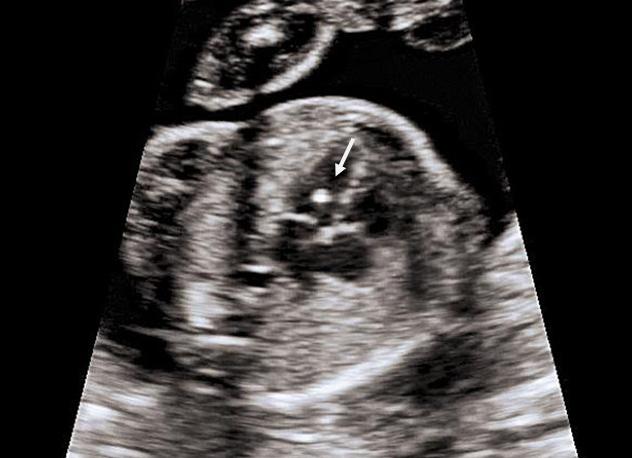

Фото 1. Гиперэхогенный фокус в левом желудочке сердца плода.

Этот феномен еще называют такими терминами как «golfball» или «мяч для гольфа (гольфный мяч)». Ее можно увидеть на фото плода как белую точку в области сердца. Когда сонолог рассматривает ее в определенном сечении и масштабировании, он видит округлое образование, которое ритмично подпрыгивает при сокращениях миокарда (отсюда и название).

Гиперэхогенный фокус сердца плода подразумевает наличие уплотнения в структуре сердечной мышцы. В результате ультразвуковые волны в большей степени отражаются от участка миокарда и дают светлое пятно на экране. Включение, как правило, имеет диаметр 2—3 миллиметра.